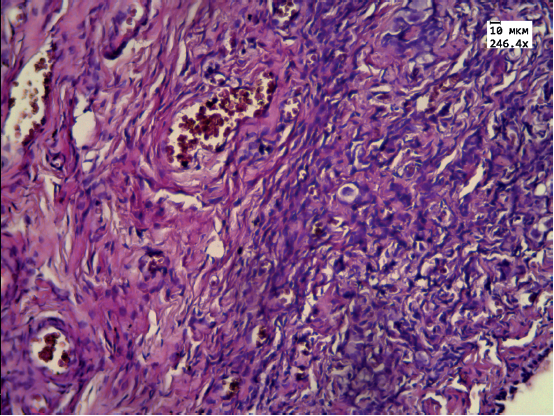

A 46,XY ovotesticular disorder of sexual development is a rare variant of pathological gonadal differentiation. A 15-month-old patient had ambiguous external genitalia, no palpable gonads, and the 46,XY karyotype. The uterus was detected by imaging of the lesser pelvis. Gonads resided on the fallopian tubes and macroscopically resembled ovotestes: each gonad consisted of two compartments separated by a connective tissue interlayer. Histological examination showed that one gonadal portion consisted for ovarian tissue, was differentiated into the cortical and medullary matter, and contained primordial follicles with pronounced dystrophic changes. The remaining portions consisted of immature tubular epithelium with proliferative cellular changes. The decision about bringing up as a female with possible adaptation during puberty was justified in this case. The surgical approach was selected on the basis of histological examination and a decision on performing gonadectomy was made.

3. Рис. 1. Микроскопическая картина ткани яичника: диф- ференцировка на корковый и мозговой слой, в корковом слое примордиальные фолликулы с дистрофическими изменениями. Окраска гематоксилином и эозином, ув. 250. | |

4. Рис. 2. Микроскопическая картина ткани яичка: эпителий канальцев незрелый, с дистрофическими и пролифера- тивными изменениями. Окраска гематоксилином и эозином, ув. 250. | |